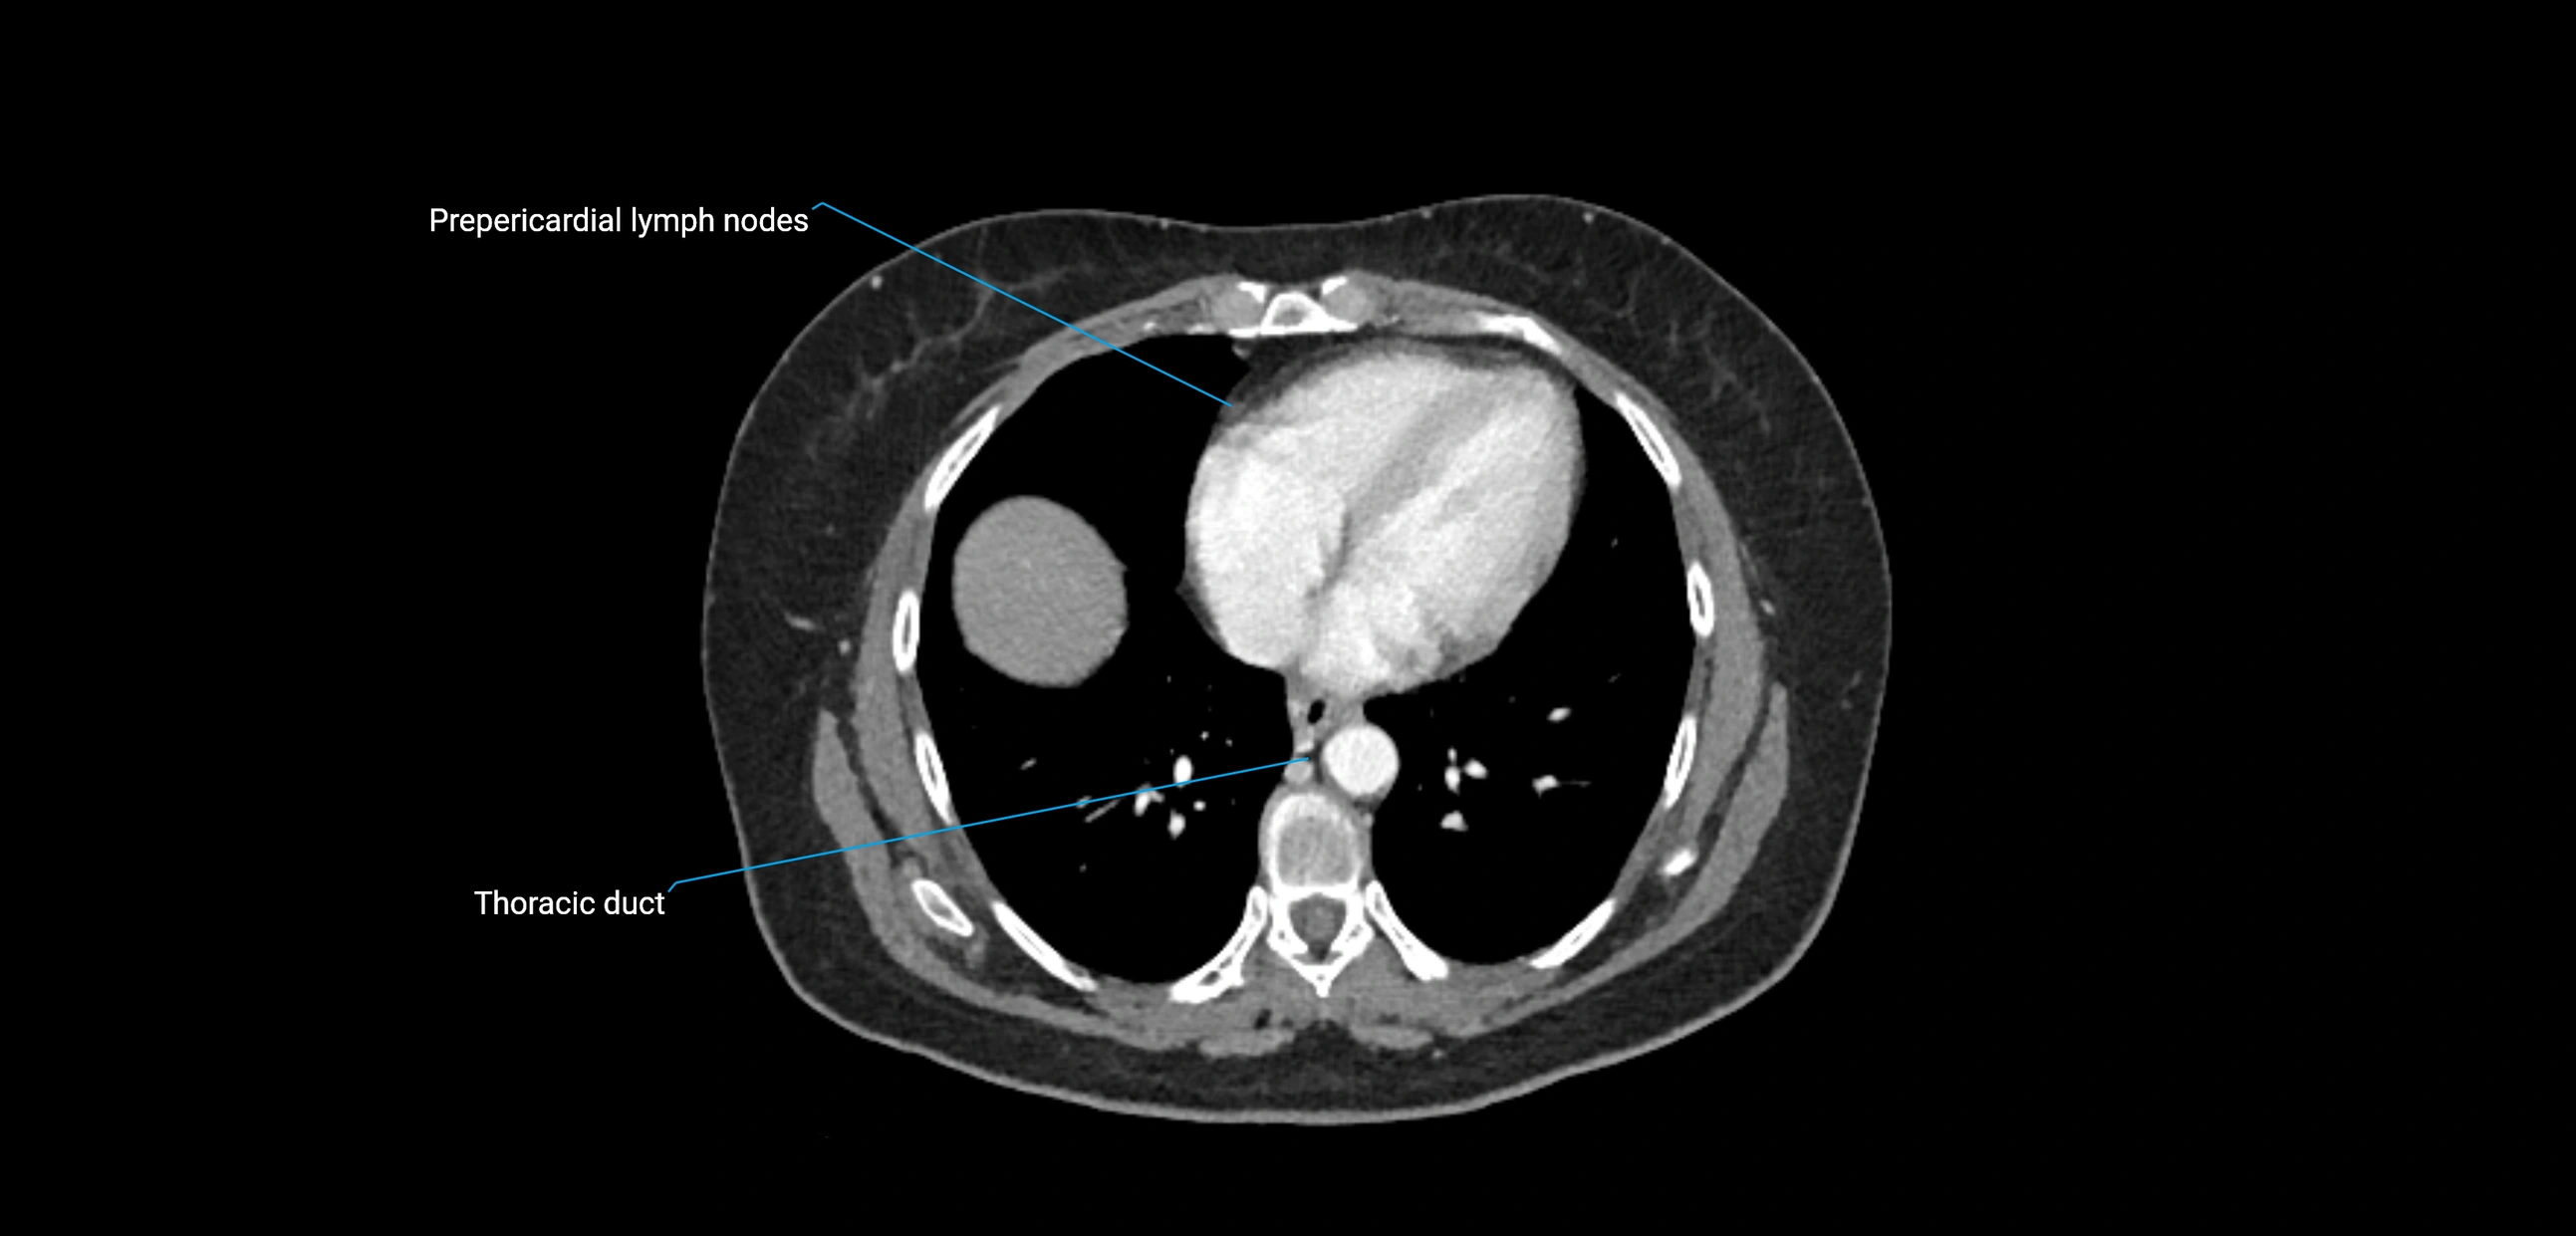

CT Appearance

CT Post-Contrast:

• Normal nodes enhance homogeneously

• Malignant nodes may show heterogeneous enhancement, central necrosis, or conglomerate formation

• Size >1 cm short axis is suspicious, though morphology and distribution are equally important

CT Venography (CTV):

• Demonstrates nodal encasement or compression of adjacent vessels (aorta, IVC, renal veins)

• Useful in staging testicular and ovarian malignancies

• Provides 3D reconstructions for retroperitoneal lymph node dissection planning